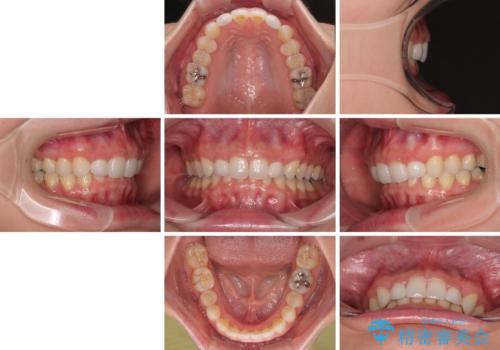

前歯のデコボコと小さい歯を改善 インビザラインとオールセラミッククラウン

- 前歯のデコボコと左右の矮小歯を気にして来院された患者様です。

矮小歯の前後にスペースを作るようにインビザライン矯正治療を計画し、矯正治療後にオールセラミッククラウンによる補綴治療を行うこととしました。

アンカースクリューを用いて上顎歯列全体を後方移動させ、極力過蓋咬合も改善されるよう計画しました。

インビザラインは長時間装着を自己管理する必要がありますが、残念ながら十分な時間の装着を行うことができませんでした。

何とか矮小歯を改善するスペースを作ることはできましたが、過蓋咬合を改善するには至りませんでした。